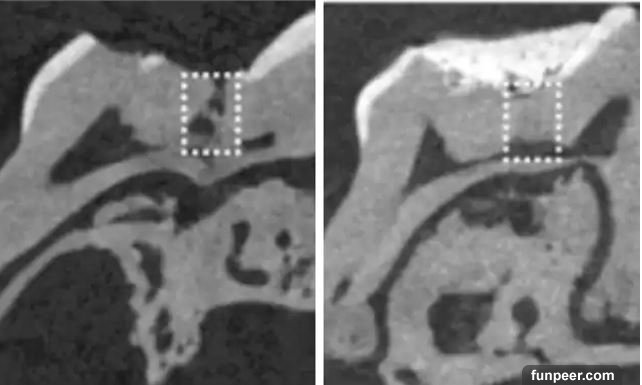

牙齒本身的自我修復能力,通常只能修復象牙質的小裂縫,然而科學家發現治療阿茲海默症的藥物能夠讓牙髓中的幹細胞活化,大幅增強牙齒的自然復原能力,讓細胞自行填補蛀牙造成的破洞。Paul Sharpe表示,我們的牙齒不只是礦物,它們還有屬於自己的生理機能。這項新技術所能夠辦到的,是讓它重新恢復生命。                                                                                                         研究團隊先使用老鼠進行實驗,他們發現,將能夠進行生物分解的小海綿浸泡Tideglusib藥物,再將其置入蛀牙處,6週後,海綿自行分解,蛀洞生成了全新的健康象牙質。更重要的是,Tideglusib在臨床使用上十分安全。牙醫Winnie Wong也相當看好這項新技術,表示:「沒有什麼東西能比得上牙齒原本的結構,所以這對蛀牙病患來說會是一大福音」。